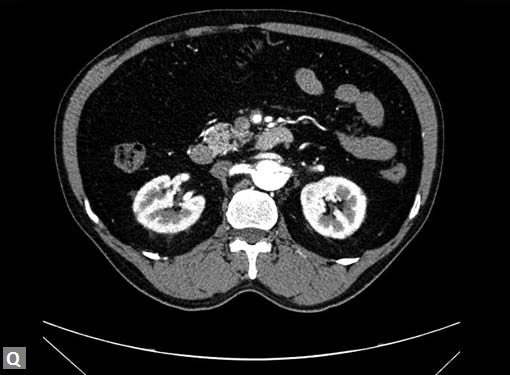

Connective tissue disease, hypertension and iatrogenic (Figs 19K to L) injury are the common causes for dissection. Radiologist not only establishes the diagnosis, also evaluates the extent of dissection, presence of thrombosis particularly in false lumen. In case of type A dissection, involvement of aortic root is determined. Relation of thrombosed lumen and ostia of coronary vessels, cephalad branches (Figs 19N, R to V) of aorta is determined. Most of the occasions membrane is demonstrated. Spiral nature of the membrane can be seen

generally enhances late compared to true lumen and

this should not be misinterpreted as thrombus. Delayed

second phase reveals the filling of pseudolumen if it is not

thrombosed. Occlusion of major vessels arising from the

thrombosed pseudolumen can result in ischemia/infarction

of organs/structures supplied by these vessels. Pain in loin

due to renal infarct may be presenting feature of a dissection.

Figs 19A to Y (A to C) Scannogram (A), plain (B) and contrast study (C) show partial anomalous pulmonary venous connection; (D to F) Heterotaxy; (G) Aortic occlusion; (H and I) Aortic stents; (J) Aortic dissection with ‘Benz’ sign due to second dissection within the true lumen; (K, L and M) Aortic dissection with thrombus in pseudolumen following catheter angiogram; (N) Aortic dissection involving common carotid arteries and subclavian artery; (O, P, Q and R) Aortic dissection with right renal artery arising from true lumen and left renal artery from false lumen; (S, T, U and V) Stanford B dissection with extension Y to iliac vessels; (W to Y) Aneurysmal dilation of ascending aorta